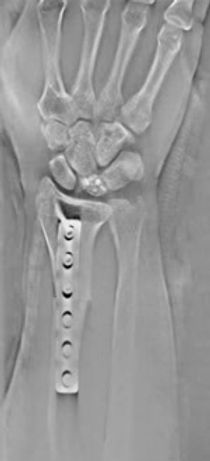

High-resolution images with minimal metal artifacts

The combination of high-resolution FPD and advanced imaging technology provides tomosynthesis images with excellent resolution, which are highly appreciated in the diagnoses of a micro-fracture, for example.

Another clinical key benefit of tomosynthesis images is the minimum influence by the metal artifacts that are usually seen on CT images. Therefore, tomosynthesis is nowadays spotlighted in orthopedics for the follow-up diagnosis of patients with metal implants.